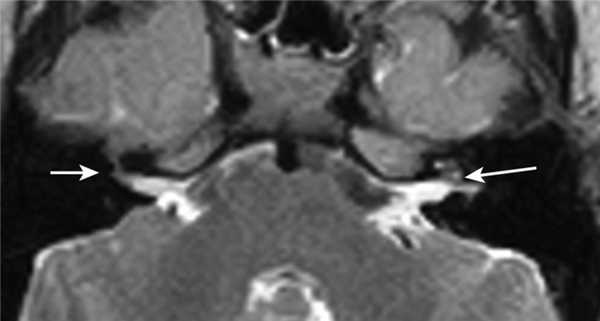

Один пациент, по данным КТ височных костей, имел двустороннюю облитерацию лабиринта, включая улитки с двух сторон, с большей выраженностью патологических изменений справа. На МРТ было выявлено уменьшение количества жидкости в улитке справа, слева количество жидкости в улитке соответствовало норме (рис. 1, 2).

Рис. 2. МРТ, аксиальная проекция. Справа — полное отсутствие жидкости в улитке (короткая стрелка), слева — частичное (длинная стрелка).